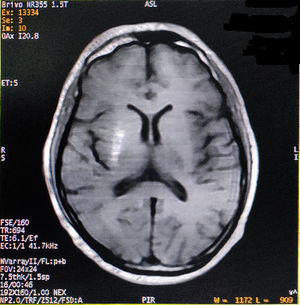

He had consulted several physicians and one neurologist for the last one month before visiting us. The initial phenomenon was diagnosed as left-sided HFS, but etiologic diagnosis remained elusive. On probing, he complained of malaise, increased thirst, and excessive frequency of urination and generalized weakness for last few days. Past medical, surgical and family history was unremarkable, except both his parents were having type-2 DM. His vital signs were all stable. Neurological examination displayed left-sided HFS along with predominantly left upper limb monochorea and subtle truncal chorea (video, see supplementary data associated with this article). His cognitive functions were intact. The patient's oropharyngeal swab test for SARS-CoV-2, by qualitative real-time reverse-transcriptase–polymerase-chain-reaction assay, was negative. Measured capillary blood glucose level was 640mg/dL. Complete blood cell count, liver, kidney and thyroid function tests were normal. Arterial blood gas analysis, serum electrolytes, C-reactive protein, urine and plasma ketones, electrocardiography, chest-X-ray, abdominal ultrasound, and blood and urine cultures were negative too. Cerebrospinal fluid (CSF) study excluded infectious etiologies. HbA1c was 8.1%. Type-1 DM was excluded as the tests for anti-GAD 65 antibodies, anti-islet cell antibodies, anti-insulin antibodies, and anti-IA2 (protein tyrosine phosphatase) antibodies were negative. On the other hand, serum fasting C-peptide level was 3.80 ng/ml (normal 0.81–3.85). Computed tomography (CT) scan of the brain and temporal bones with intravenous contrast was normal. Brain magnetic resonance imaging (MRI) revealed right striatal hyperintensity on T1-weighted imaging (Fig. 1). Magnetic resonance angiogram of the brain was otherwise normal. Acute symptomatic hyperglycemia associated with predominantly left upper limb monochorea and left-sided HFS with striatal abnormalities on neuroimaging pointed towards a diagnosis of diabetic striatopathy due to non-ketotic hyperglycemia. Continuous intravenous insulin infusion and rapid rehydration with intravenous fluids and were started.

After two days, blood glucose level stabilized. The abnormal movements reduced in frequency and intensity, but persisted with sustained normalization of blood glucose levels. He was discharged after seven days with a basal-bolus regime of insulin and diabetic medical nutrition therapy. The patient was followed-up at regular intervals with achievement of good glycemic control and no evidence of exacerbation of abnormal movements (though subtle infrequent unilateral HFS and mild choreiform movements in the left upper limb were persisting). On follow-up visit after six months, a new brain MRI was performed showing partial resolution of the striatal lesion.